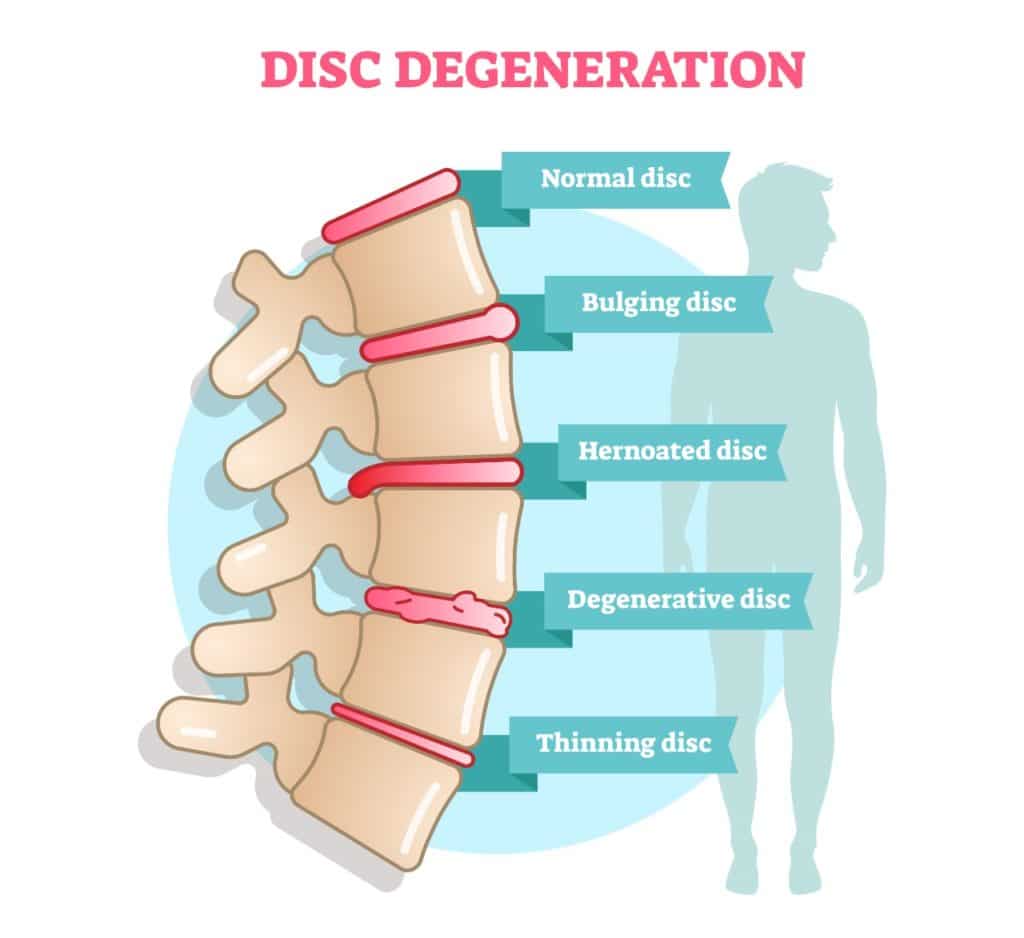

What are the different types of disc problems? | QI Spine

Bulging Discs And How You Can Slow Them Down

Bulging and Herniated Discs – Explained | Physical Health Care

What is the difference between a bulging disc and a herniated disc?